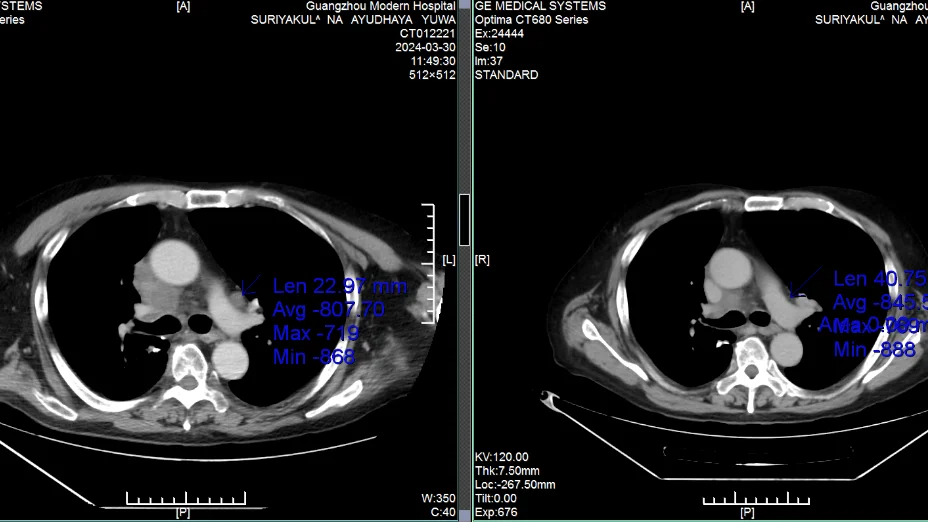

เขาถูกวินิจฉัยว่าเป็นมะเร็งปอดในปี 2021 และเข้ารับการผ่าตัดรวมถึงเคมีบำบัด–รังสีบำบัดในประเทศไทย แต่โรคยังคงกลับมาและแพร่กระจาย เนื่องจากอายุมากและมีความดันโลหิตสูงขั้นรุนแรง ทำให้ไม่สามารถรับการรักษาแบบดั้งเดิมได้อีก ในเดือนมีนาคม 2023 หลังมาถึงโรงพยาบาล ทีม MDT ได้ทำการรักษาแบบคีโมเฉพาะจุดไมโครอินเวซิฟร่วมกับการฝังเม็ดรังสีและการรักษาภูมิคุ้มกัน เพียง 2 ครั้ง เนื้องอกลดลง 60% อาการหายใจลำบากหายไป จากที่ต้องนั่งรถเข็นตอนเข้ารักษา ก็สามารถเดินได้ด้วยตนเอง คุณภาพชีวิตดีขึ้นอย่างเห็นได้ชัด